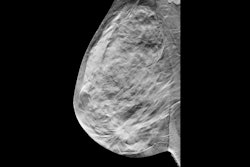

The combination of contrast-enhanced mammography (CEM) and digital breast tomosynthesis (DBT) increases early breast cancer detection each year in women with a personal history of the disease – although it also increases the recall rate, researchers have found.

"Adding contrast-enhanced mammography (CEM) to digital breast tomosynthesis substantially improved the detection of early breast cancer in women with a personal history of breast cancer, and this benefit appears to persist each year," wrote a team led by Wendie Berg, MD, PhD, of the University of Pittsburgh in Pennsylvania in an article published April 30 in Radiology.

The findings are good news for women with a history of breast cancer, as DBT can be insufficient for screening them, Berg's group explained. An ongoing trial called Tomosynthesis or Contrast-Enhanced Mammography (TOCEM) is investigating the use of three annual screenings with both DBT and contrast-enhanced mammography (CEM) for women with breast cancer history; the group conducted a study using data from this trial.

Berg's and colleagues' study tracked three years of results (October 2019 to December 2022), with 1,273 women participating in year one, 819 in year two, and 227 in year three; all of the women underwent a DBT exam and a CEM exam. Two radiologists interpreted both examinations. Berg's group evaluated the effect of adding CEM to DBT on incremental cancer detection rate, cancer type and node status, and recall rate.